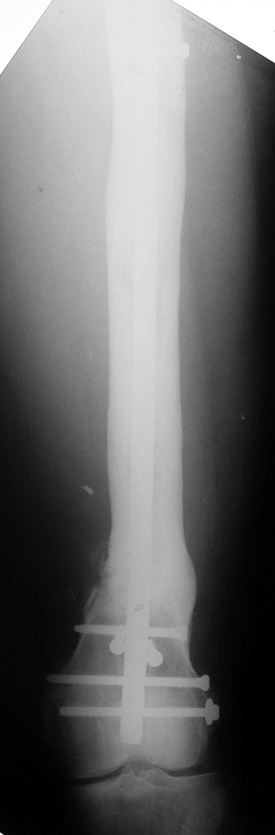

Vaka 3